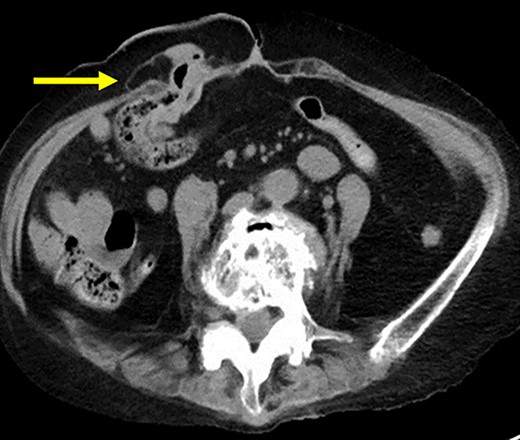

A 75-year-old woman underwent sigmoid colon resection and transverse colostomy for perforation of the diverticulum of the sigmoid colon at 70 years of age at another hospital. The colostomy was performed in the right upper quadrant. She was referred to our hospital with complaints of abdominal discomfort 3 months prior to presentation. She had a history of rheumatoid arthritis and took steroids. Abdominal computed tomography (CT) revealed PSH with loss of fascia around her ostomy. The defect measured ~65 × 60 mm. Herniation of the transverse colon was observed (Fig. 1). No abdominal wall hernia was found, and the diagnosis was European Hernia Society (EHS) type III.

(a) CT scan revealed a prolapse of the transverse colon on the oral side (arrow); (b) CT scan revealed a prolapse of the transverse colon on the anal side (triangle).